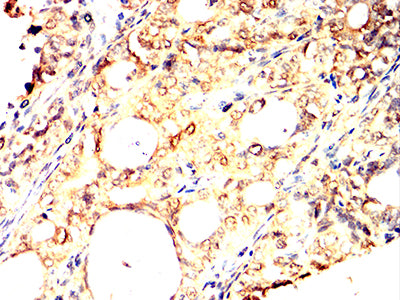

Immunohistochemical analysis of paraffin-embedded human cervical cancer tissues using ULK3 mouse mAb with DAB staining.

Immunohistochemical analysis of paraffin-embedded human prostate cancer tissues using ULK3 mouse mAb with DAB staining.